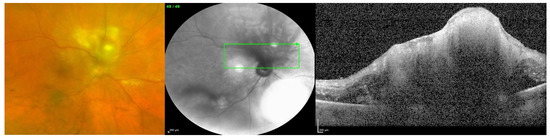

Endogenous endophthalmitis refers to the hematogenous dissemination of organisms causing intraocular infection. Endogenous endophthalmitis is less common, should be considered in the setting of fungemia, and is associated with specific risk factors [1]. Systemic immunosuppression without fungal bloodstream penetration is not considered a definitive risk factor; rather, the risk is in the combination of both. Examples of factors that can lead to penetration of the bloodstream by fungi include long-term indwelling intravenous catheters, prolonged hospital stays, abdominal surgery, and intravenous drug use. [4,5]. Figure 1 shows a case of endogenous fungal endophthalmitis, which was identified and correlated with a history of intravenous substance abuse, one of the definitive risk factors. Figure 2 also displays a case of endogenous fungal endophthalmitis, with a lesion characteristic of typical infection. When it comes to identifying the specific fungal species responsible for endogenous fungal endophthalmitis, the most frequently encountered organisms include Candida albicans and Aspergillus [6,7]. Other causative microorganisms include C. dulineniesis, C. tropicalis, and A. niger [6,7]. However, the precise proportions can vary depending on the data reported in the literature. In a study involving 27 cases of endogenous endophthalmitis, Binder et al. observed that among their 14 patients with fungal infections, 10 had Candida albicans infections (accounting for 71.4%), while 4 had A. fumigatus infections (28.6%) [8]. In contrast, Mir et al. examined a much larger sample of 56,839 cases of endogenous endophthalmitis and found that Candida infections were present in 6.7% of cases, while Aspergillus infections occurred in 0.4% of cases [5]. Additionally, in a study of 57 cases of endogenous endophthalmitis conducted by Lim et al., they identified C. albicans as the most common fungal cause, occurring in 9 cases (15.8%) [9]. Taken together, these findings suggest that yeasts, particularly Candida species, appear to be more commonly associated with endogenous fungal endophthalmitis, while molds, particularly Aspergillus and fusarium, are more frequently implicated in exogenous fungal endophthalmitis. However, it is important to note that a direct comparison or conclusive statement on this matter has not been formally studied or established.

Figure 2. Endogenous fungal endophthalmitis in a patient with multiple bowel surgeries and progressive bilateral vision loss. Wide-field fundus photo of the right eye shows characteristic creamy-white lesions in the retina and vitreous opacities.